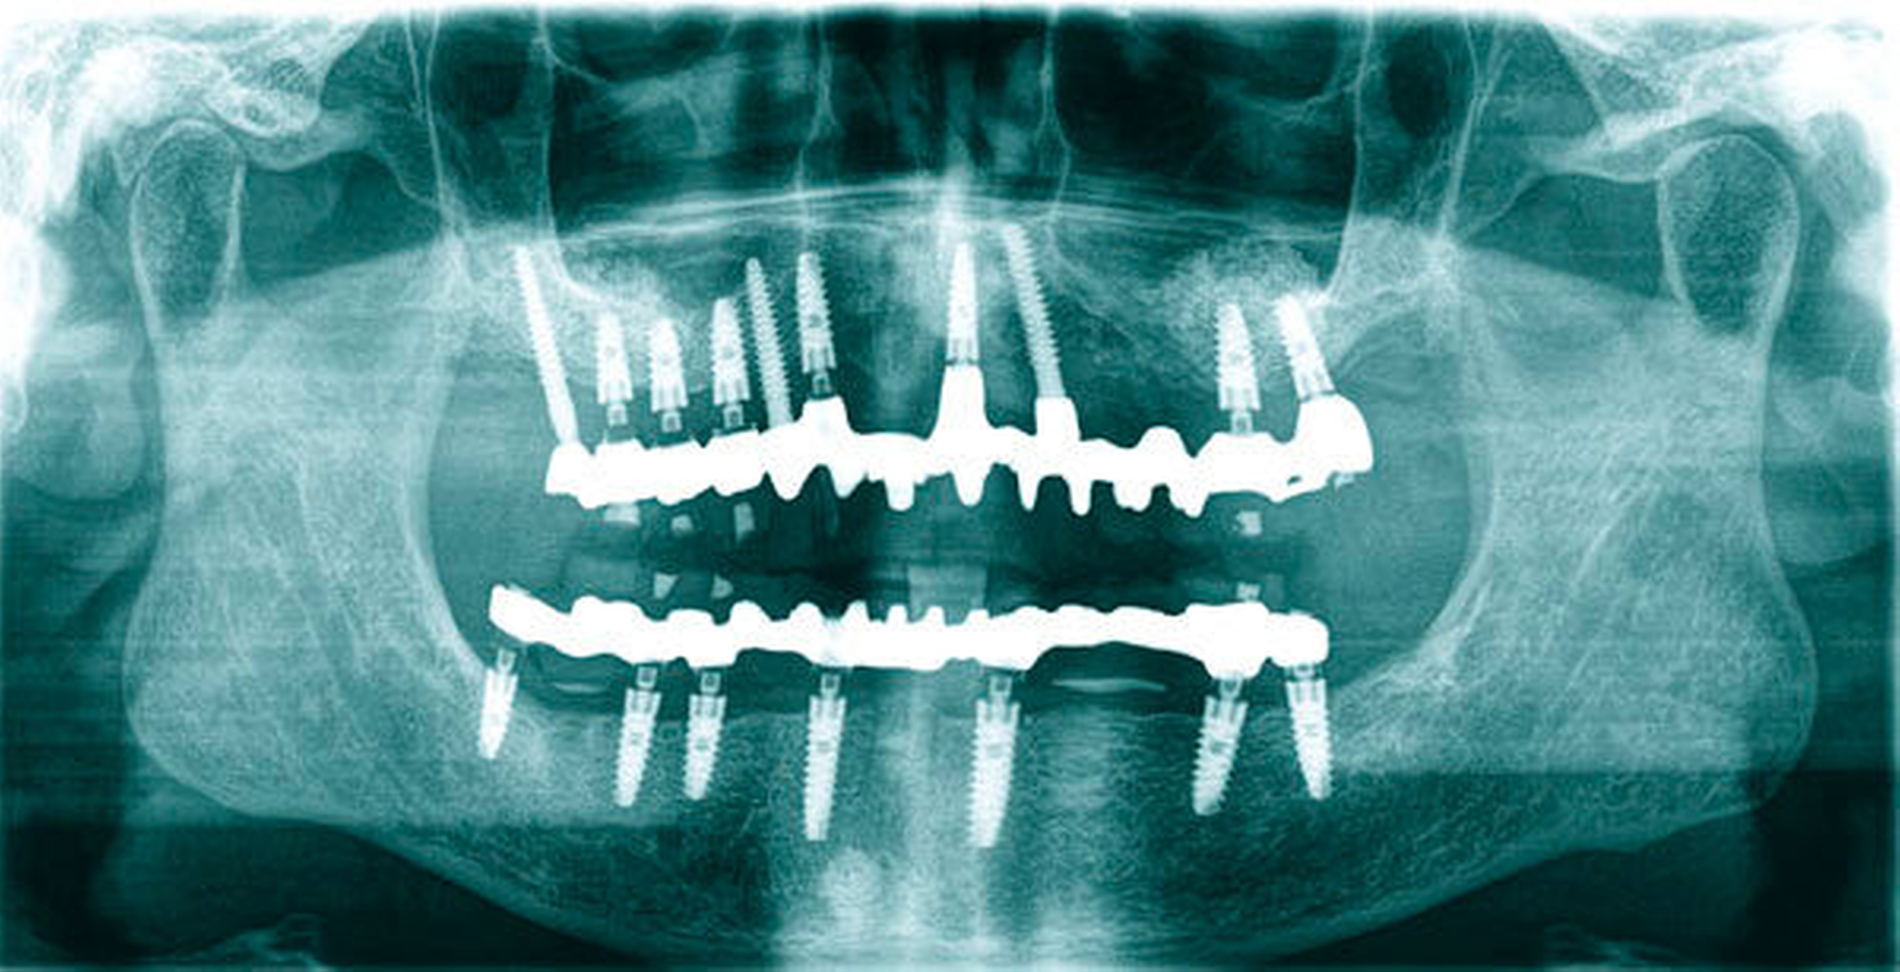

Die chirurgische Platzierung von Zahnimplantaten, das heißt die eigentliche Implantation, und die nachfolgende prothetische Versorgung dieser Implantate liegen nicht immer in einer Hand, sondern werden zum Teil von zwei verschiedenen Behandlern durchgeführt. Eine solche Arbeitsteilung hat durchaus Vorzüge: Aus der Allgemeinchirurgie wissen wir, dass Operateure mit großer Behandlungsroutine (hohe Fallzahlen pro Jahr) signifikant bessere Ergebnisse erzielen [Halm et al., 2002]. Doch geteilte Zuständigkeiten bergen auch Fallstricke: Wenn die Implantation und die nachfolgende prothetische Versorgung nicht gemeinsam geplant oder zumindest aufeinander abgestimmt werden, stellen sich im Fall eines ungünstigen Endresultats (Behandlungsfehler-Vorwurf) Fragen der Verantwortlichkeit. Man denke etwa an einen Fall, in dem ein Fachchirurg Implantate setzt, die aus Sicht des Implantatprothetikers falsch positioniert sind (Abbildungen 1, 2, 4, 5 und 6).

Letzterem bleibt nur die Wahl zwischen der Ablehnung der Weiterbehandlung und der Empfehlung einer aufwendigen und substanzverlustträchtigen Revision der Implantate (beides mutet dem betroffenen Patienten einiges zu) oder einer „Kompromissbehandlung“ mit dem Ziel, die invasive Revision der gesetzten Implantate abzuwenden und so den Schaden für den Patienten zu begrenzen. Heikel wird es insbesondere dann, wenn der Prothetiker in bester Absicht eine solche Kompromissbehandlung wagt, diese sich aber als nicht alltagstauglich erweist und der Patient schlussendlich Klage erhebt.

Hier kann es unter Umständen schwerfallen, die Verantwortung zuzuweisen: Liegt die Schuld beim Chirurgen, der die Implantate an ungünstiger Stelle gesetzt hat, oder beim Prothetiker, der sich nolens volens auf diese Situation eingelassen und ein letztlich unzureichendes Behandlungsergebnis erzielt hat? Aus fachlicher und ethischer Sicht ist die eigentliche Ursache für das insuffiziente Behandlungsergebnis beim Chirurgen zu suchen. Juristisch gesehen trägt dagegen jedoch der Implantatprothetiker die unmittelbare Verantwortung für das Behandlungsergebnis, da er die insuffiziente Suprakonstruktion geplant und eingegliedert hat. Rechtlich verhängnisvoll wird dieses Vorgehen insbesondere dann, wenn er den Patienten nicht explizit über den Kompromiss- und Versuchscharakter seiner Versorgung aufgeklärt hat oder das Aufklärungsgespräch und das Einverständnis des Patienten zur eigenen juristischen Absicherung nicht sorgsam dokumentiert hat.